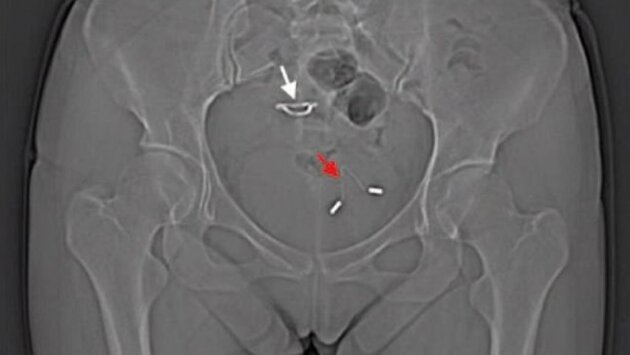

Врачи обнаружили в мочевом пузыре 26-летней женщины внутриматочную спираль через годы после того, как она забеременела и родила, несмотря на использование этого контрацептива. Женщина прибыла в больницу с жалобами на боль в животе.Китайские врачи раскрыли загадку, которая мучила длительное время 26-летнюю пациентку. Долгие годы она испытывала странную боль в животе, но не могла понять, с чем она связана. Оказалось, что еще в 2011 году девушка установила себе внутриматочную спираль, однако через несколько месяцев она забеременела, а в феврале 2012 произвела на свет ребенка. Малыш появился благодаря кесареву сечению, и врачи при этом не обнаружили никакого следа внутриматочной спирали. Они предположили, что каким-то образом она сохранилась в матке. Но рентгеновский снимок тазовой области позволил ответить на вопрос, каким образом девушка забеременела, несмотря на использование контрацептива. Оказалось, что спираль перфорировала матку и проложила себе путь прямо в мочевой пузырь, что и вызвало осложнение, связанное с мочевыводящими путями.Описывая этот случай в одном из научных журналов, врачи подчеркивают, что перфорация матки является одним из самых странных осложнений, которые можно только представить при использовании внутриматочных спиралей. Это осложнение наблюдается у одной женщины из каждой тысячи, устанавливающих спирали. Однако поскольку далеко не всегда это сопровождается какими-либо симптомами, то на самом деле число столкнувшихся с данным осложнением может быть даже ещё выше. На способность вызывать подобные осложнения влияет целый ряд факторов, включая разновидность использованной спирали, а также время ее установки и квалификацию врача.Когда спираль прокладывает себе путь внутрь тела, она может проникнуть довольно глубоко. После перфорирования матки спираль могут обнаружить даже в брюшной полости, как подчеркивают ученые.